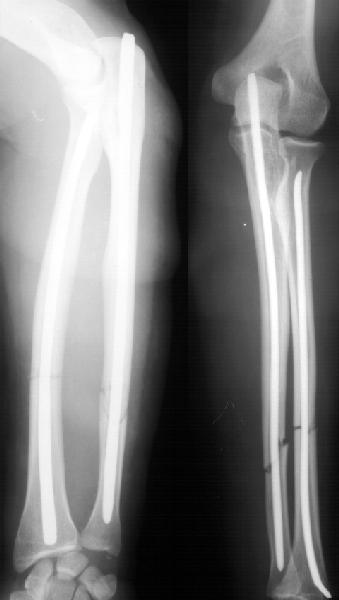

А зачем же неправильный гвоздь использовать, который нарушает? Наоборот, с помощью гводя нарушенная форма костей очень даже эффективно восстанавливается (см. пример). А неправильный

остеосинтез можно сделать чем угодно.

>Наоборот, с помощью гводя нарушенная форма костей очень даже эффективно восстанавливается (см. пример).

форма восстанавливается, но достаточной стабильности при таком остеосинтезе (пример) достигнуть трудно, ранние движения невозможны, а несращения встречаются как и при любом виде остеосинтеза.

Эта конкретная больная на пятый день после операции мыла дома пол (муж - хирург, не мог же он этим заниматься :-)

А движения как раз начинаются максимально рано, на следующий день, включая ротацию - больших ран ведь нет, сильно не болит - в приложении картина в день снятия швов.

К месяцу после операции практически у всех больных - клиническая картина здорового человека.

Так что стабильность достаточная. А то, что она не абсолютная, как с пластинкой - это как раз способствует периостальному сращению. Конечно, при многооскольчатых переломах для осевой устойчивости лучше запирать винтами.